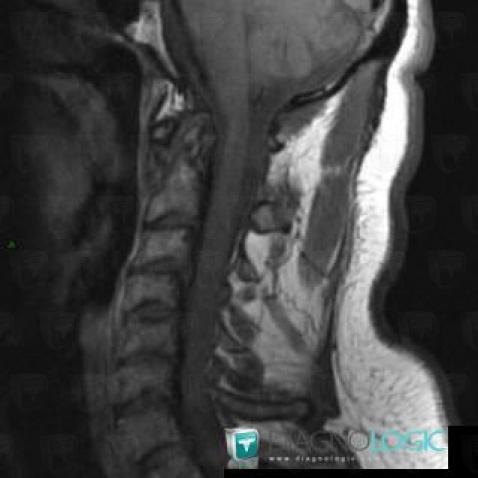

Rheumatoid arthritis, Vertebral body / Disk, MRI

Here is the specific information in the key image above:

- Diagnosis Rheumatoid arthritis, Location(s) Vertebral body / Disk, with gamuts